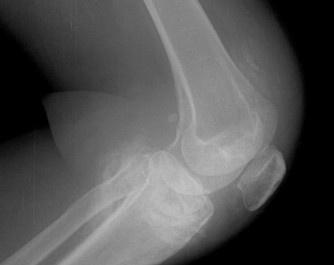

- 常見癥狀:膝關節水腫、疼痛、活動受限、跛行、膝關節屈伸活動受限、下蹲困難、并伴有疼痛、關節周圍局限性壓疼、浮髕試驗陽性

滑膜炎(英文名:synovitis),是一種多發性疾病,其發病部位主要在膝關節。膝關節是人體滑膜最多,關節面最大和結構最復雜的關節,由于膝關節滑膜廣泛并位于肢體表較淺部位,故遭受損傷和感染的機會較多,膝關節滑膜炎主要是因膝關節扭傷和多種關節內損傷,而造成的一組綜合癥。容易造成患者暫時或長期部分喪失勞動力,無論對患者和對社會的危害都較大。雖由許多有效的治療方法,但仍有許多患者仍不能治愈。尤其是部分中青年患者,要承擔許多社會和家庭責任,同時又在長期忍受疼痛的折磨。這無疑是急待醫務工作者解決的問題。